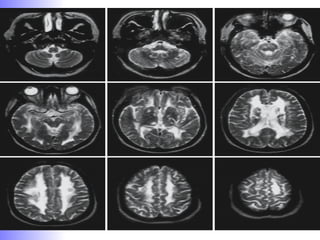

sMRI- Alzehimer’s Disease

Assessment of cerebral atrophy of hemisphere

particularly posterior temporal and parietal lobes & specific

anatomic areas like hippocampus and medial temporal

lobe

1. Visual ranking system: Mild / moderate / severe.

2. Quantitative measurement : Linear / area / volumetric*.

Measurements must be adjusted for age, gender and head

size and then referenced to an appropriate control

population.

Among these measurements of hippocampus was most sensitive

marker of pathology of AD early in disease.